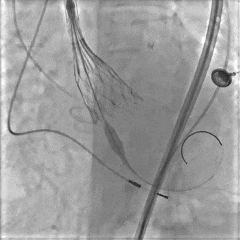

再次定位释放

大弯侧0位,形态可见压缩

小弯侧深度尚可

瓣膜脱钩,轻微自同轴

脱钩后造影,瓣膜稳定,无反流

左侧位造影,小弯侧深度尚可

预先置入8mm球囊,准备撤出大鞘

髂外动脉可见造影剂渗出,8mm球囊进行阻断

植入覆膜支架,造影可见轻微出血

植入第二条覆膜支架,无造影剂渗出,手术结束